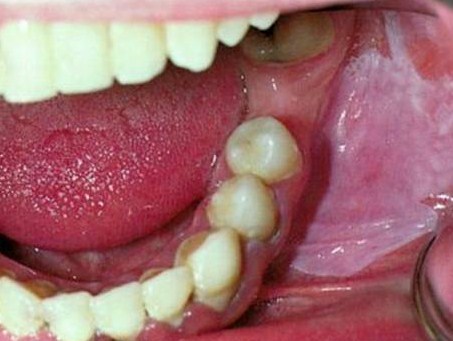

Morsicatio Buccarum

CHRONIC CHEEK CHEWING

Thickend, shredded, white areas which may be ulcerated

High prevalance in individuals under stress or with psychologic condition

No treatment required – stop the habit

Not a premalignant condition – doesn’t cause chronic inflammation